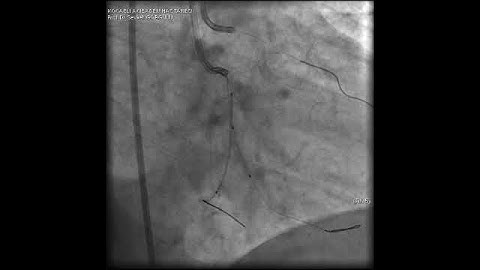

Complex PCI for RCA CTO with bifurcation at distal cap video 7